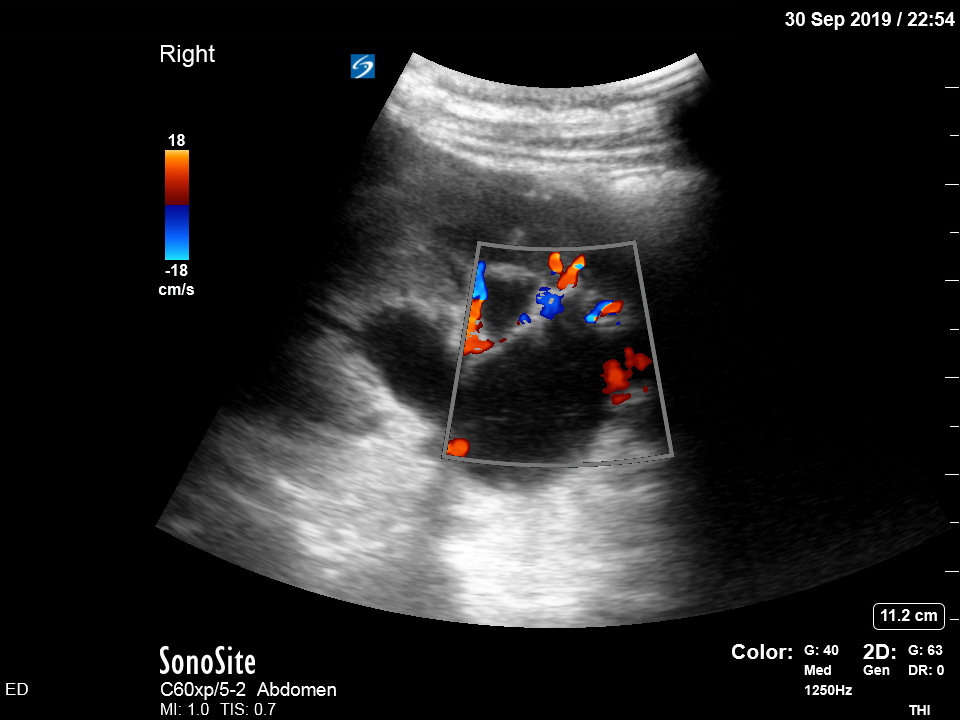

Bedside ultrasound was undertaken to assess for signs of ureteric obstruction.

There is moderate-to-severe hydronephrosis of the right kidney. There is mild hydronephrosis on the left. Colour flow doppler is used to demonstrate that the dilated pelvis and calyces are not normal blood vessels or aneurysms.

Hydronephrosis is dilation of the renal collecting system caused by increased pressure in the ureter, strongly suggesting downstream obstruction. Possible explanations for bilateral hydronephrosis include bladder outlet obstruction and bilateral ureteric obstruction. The former is unlikely in a freely urinating patient, especially female.